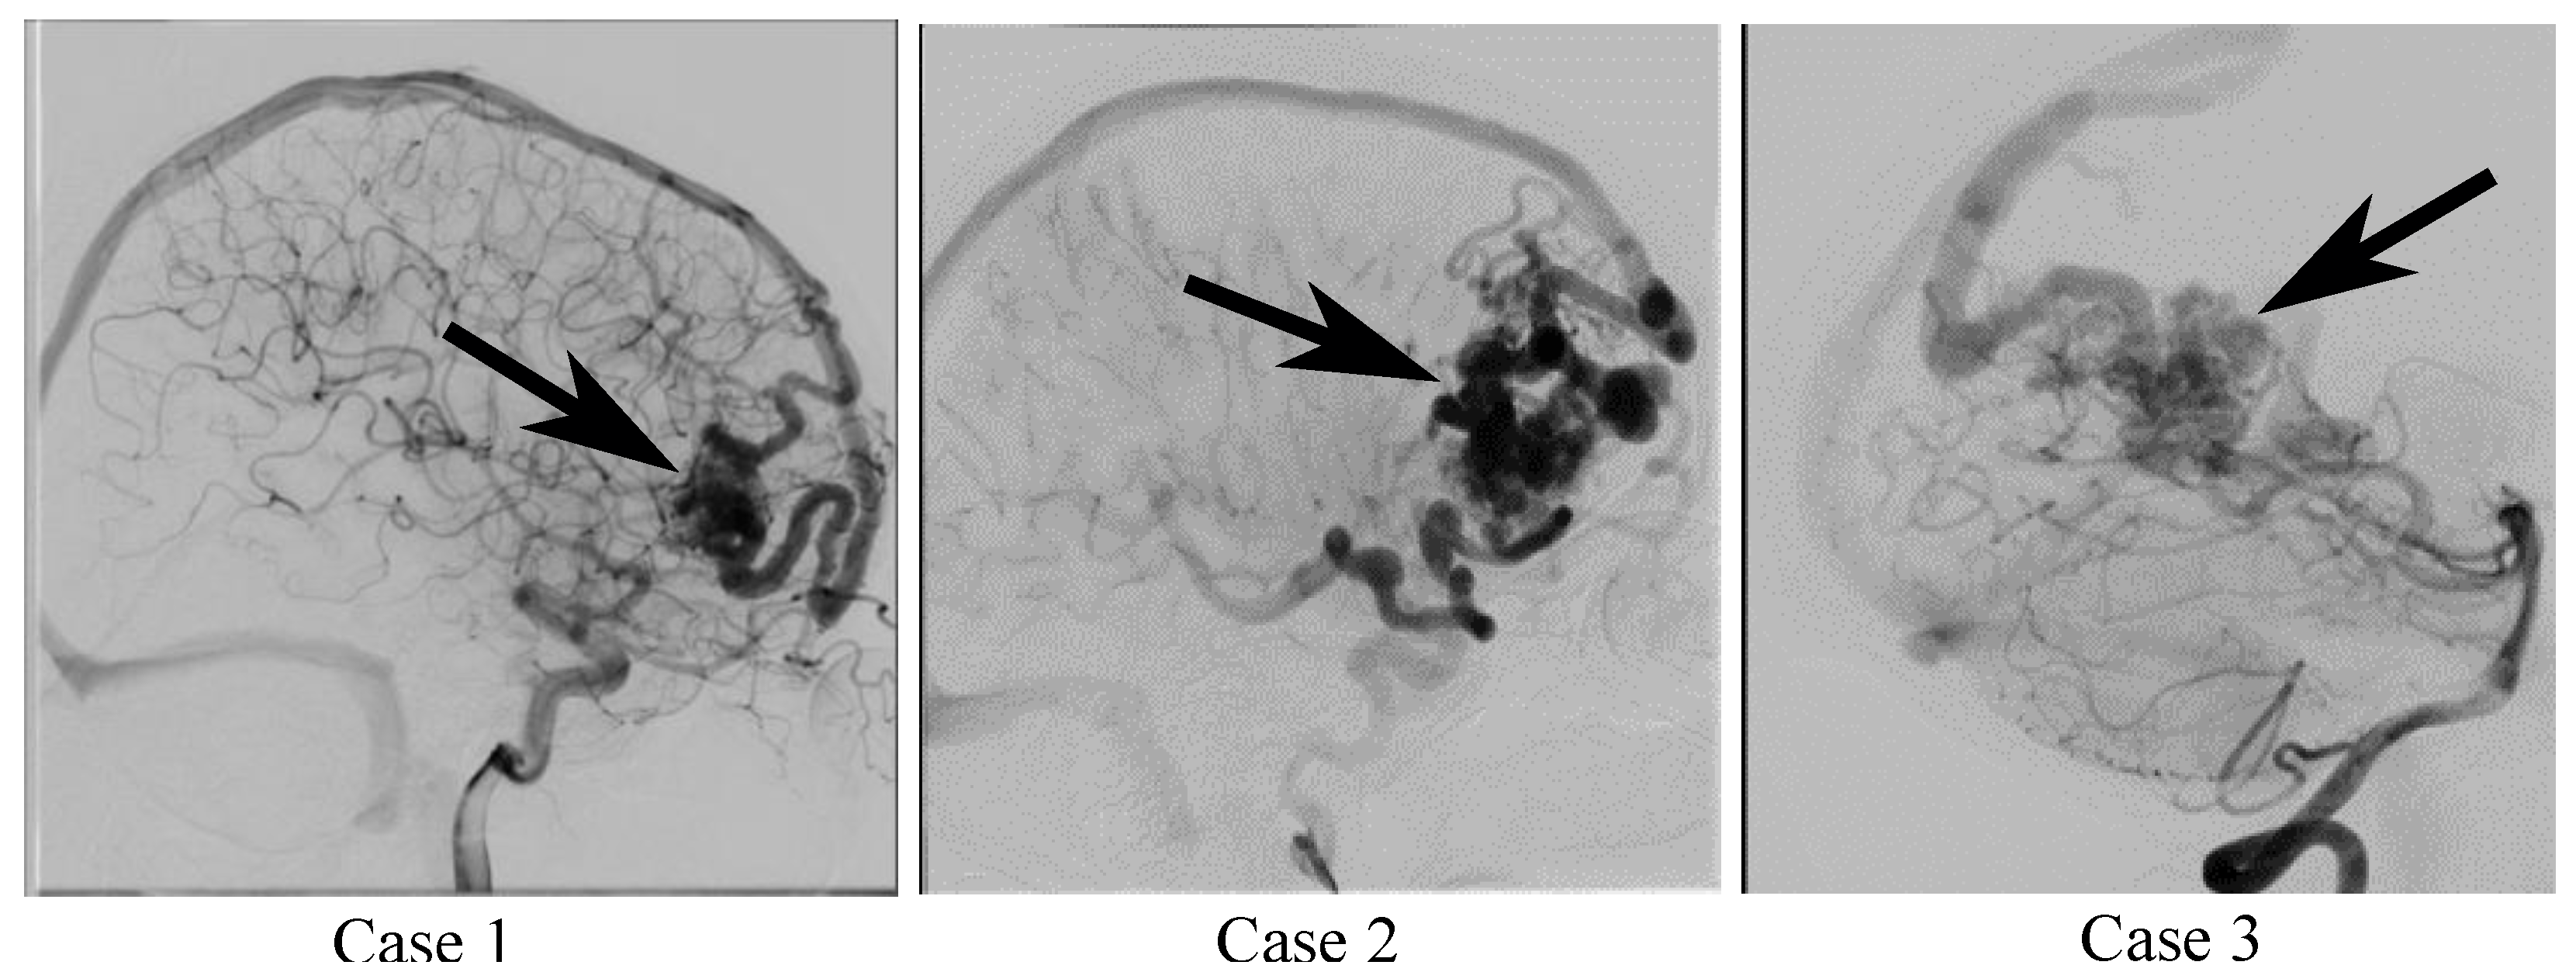

2.1. Patient and Image Data

| Case 1 | Case 2 | Case 3 | |

| Nidus location | right frontal | right frontal | right occipital |

| Number of feeding arteries | 2 | 3 | 3 |

| Number of draining veins | 3 | 2 | 2 |